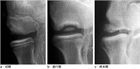

1. 主な症状は疼痛であるが、離断性骨軟骨炎の病初期では症状が乏しいことの記載に関する文献を変更した(Matsuura T, et al. JSES Int. 2024 Feb;8(3):661-666.)。

1. 離断性骨軟骨炎について症状が乏しい症例の発見には超音波検査が有用であることを記載した。